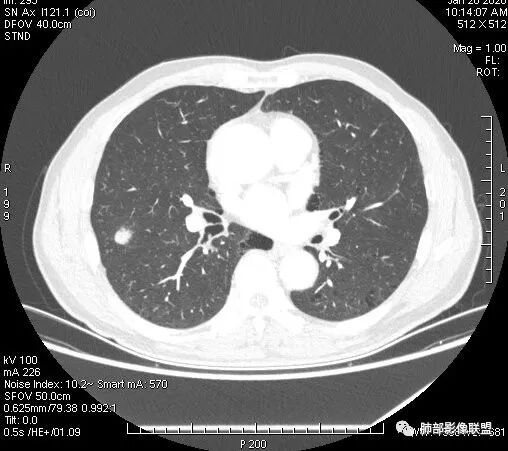

患者右上肺占位,内部强化不均,有空泡,有血管穿过,血管聚集现象,似有胸膜牵拉,考虑恶性

右肺上叶后段占位病灶,病灶不规则,周围胸膜线性牵拉,病灶部分周围有晕,病灶内见不规则空洞,未见明显引流支气管,长毛刺,多分叶、肿块边缘部分L型,可见血管直接供养。增强见点状坏死、病灶内血管。综上考虑恶性可能性大,鉴别隐球菌。

右肺上叶结节,浅分叶膨隆,边缘可见胸膜牵拉及血管集束,不规则厚壁空洞,不均匀强化,血管进入病灶,边缘毛燥,考虑低分化腺癌,鉴别隐球菌。

来个不一样的,小病灶近心端空洞,分叶,毛刺软,长,收缩力差,强化明显,血管走形自然,无明显卫星灶,先考虑炎性,肉芽肿炎,隐球菌可能性大,不排除肿瘤,需要活检

右肺团块影,深分叶,有毛刺,但毛刺偏软。团块附近有血管走行,穿过。血管增粗,僵直。空洞近心,团块周围似有卫星灶。良,恶性征象都有;按可能性排序:隐球,结核,腺癌。

右肺结节,分叶、长短毛刺,边缘略膨隆,胸膜牵拉,血管进入病灶,收缩力较弱,有血管聚集征,洞壁尚规整,低强化,坏死边缘规整。考虑炎性,隐球,鉴别腺癌。

晨读,右肺上叶结节,边缘膨隆、分叶,部分边缘有平直,可见多发毛刺及胸膜牵拉,牵拉线清秀,收缩力弱,内密度不均,可见片状低密度影及空洞,增强后不均匀强化,血管集束,考虑良性,肉芽肿性结节,鉴别腺癌

晨读:双肺胸膜下多发小气囊,大小不一,右肺结节,内部可见小空洞,洞壁光滑,厚薄不一,偏心性生长,近段血管束增粗,有分叶,毛刺(软),有晕征,平扫密度尚可,增强后不均匀强化,可见低密度坏死,及部分血管穿行,体检发现,考虑恶性:腺癌,鉴别炎性结节

晨读:右肺中叶结节,浅分叶,边缘膨隆,胸膜牵拉,不规则偏心厚壁小空洞,空洞壁可见低密度坏死,不均匀强化,血管进入病灶,边缘毛燥,考虑鳞癌。鉴别肉芽肿

右肺上叶结节,边界清,有分叶,厚壁空洞,强化后见坏死区,血管进入病灶,考虑结核。

右上叶结节,轻分叶,结节有长短不一毛刺,结节周围GGO边界清,有血管集束征,肺窗结节周围似可见卫星灶,可见鬼脸征,良恶性征象都有,但GGO边界清,浸润性腺癌耍考虑,临床症状轻微,体捡发现,似可见卫星灶和鬼脸征,炎性肉芽肿TB或隐球菌要鉴别。